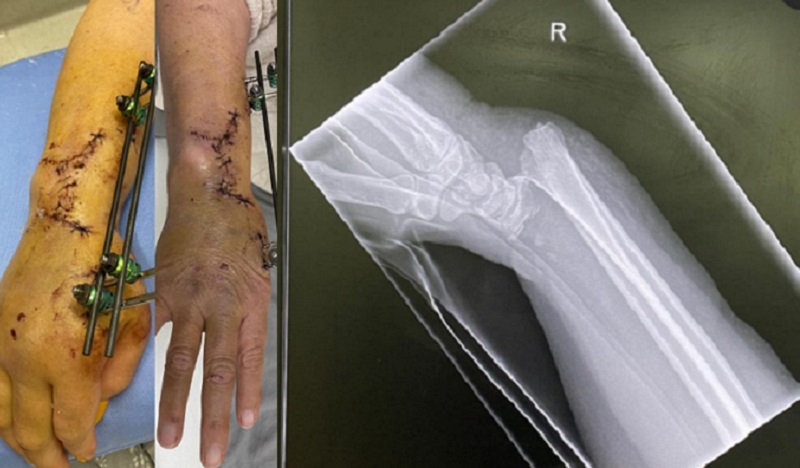

*This story contains medical images which some may find distressing

A mother and daughter from Calgary are suffering six months after a near-deadly crash on the QEII Highway near Red Deer.